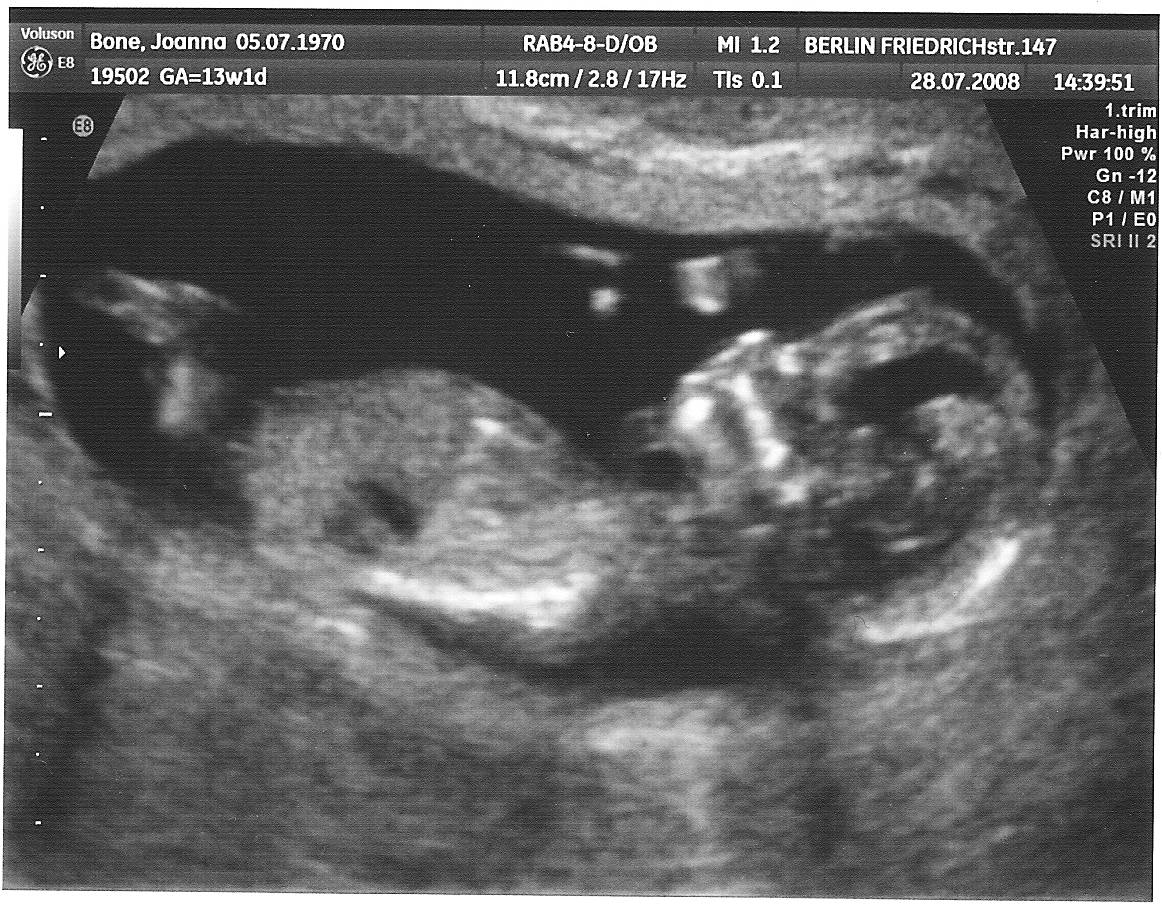

Ja też się muszę pochwalić :), miałam dzisiaj pierwsze USG, dzidzia ma 3cm :), bardzo machała rączkami, słyszałam serduszko...

usg1.jpg

To nasz rozbrykany olbrzymek zdjęcie troszkę nie najlepszej jakości bo nie mam skanera i robiłam zdjęcie zdjęciu. ale widać jak się wygięła dzidzia i rozprostowała nóżki:-)